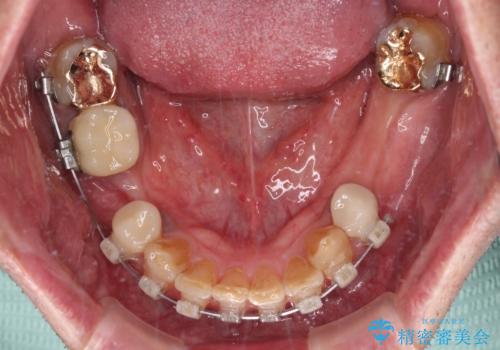

奥歯に欠損が多く、矯正治療はやや難航することが予想されますが、患者様の希望もあり、上顎左右小臼歯を1本ずつ抜歯し、ワイヤー装置にて矯正治療を行うこととしました。

矯正歯科治療を行うに当たり、痛みや違和感を感じている歯の根管治療を行い、矯正治療中にインプラント埋入し、補綴治療と矯正治療を同時に終了できるように進めて行くこととしました。